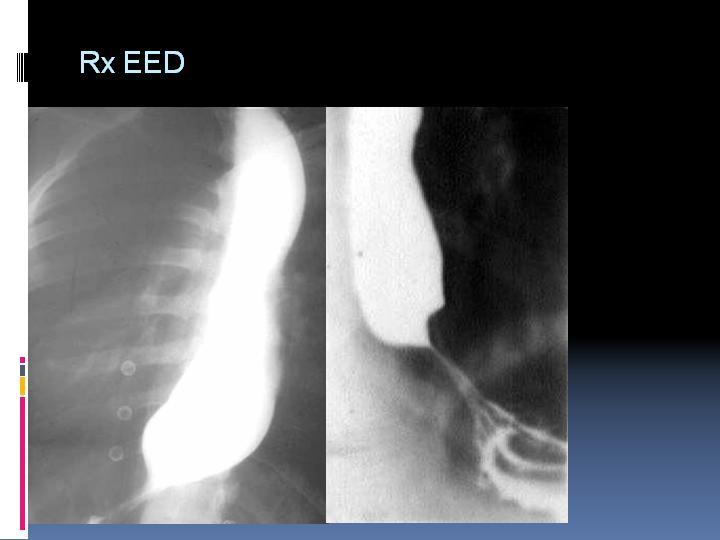

Acalasia

Digestivo Alto

| Autor: Dr. Cristóbal Davanzo C.